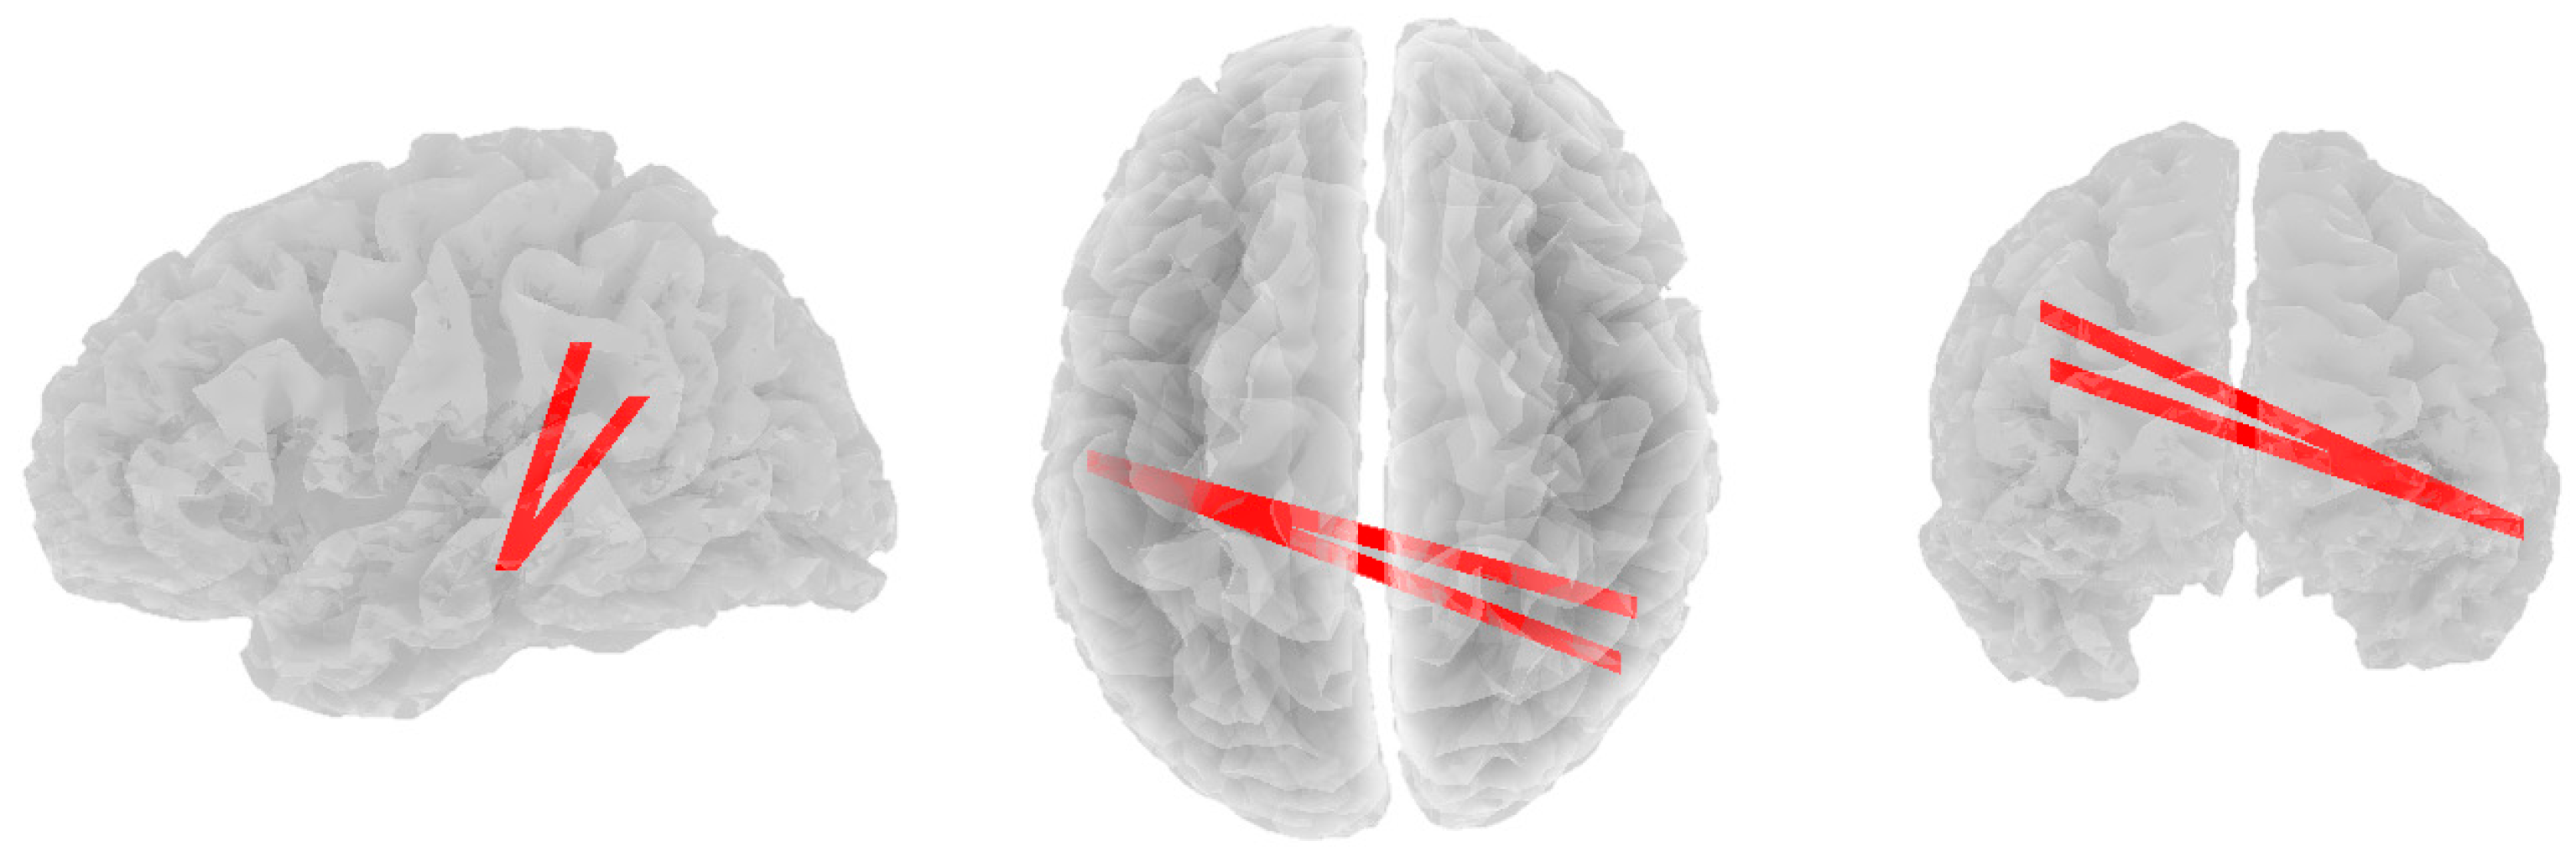

3.2. Alpha Band

3.3. Beta Band

3.4. Theta Band